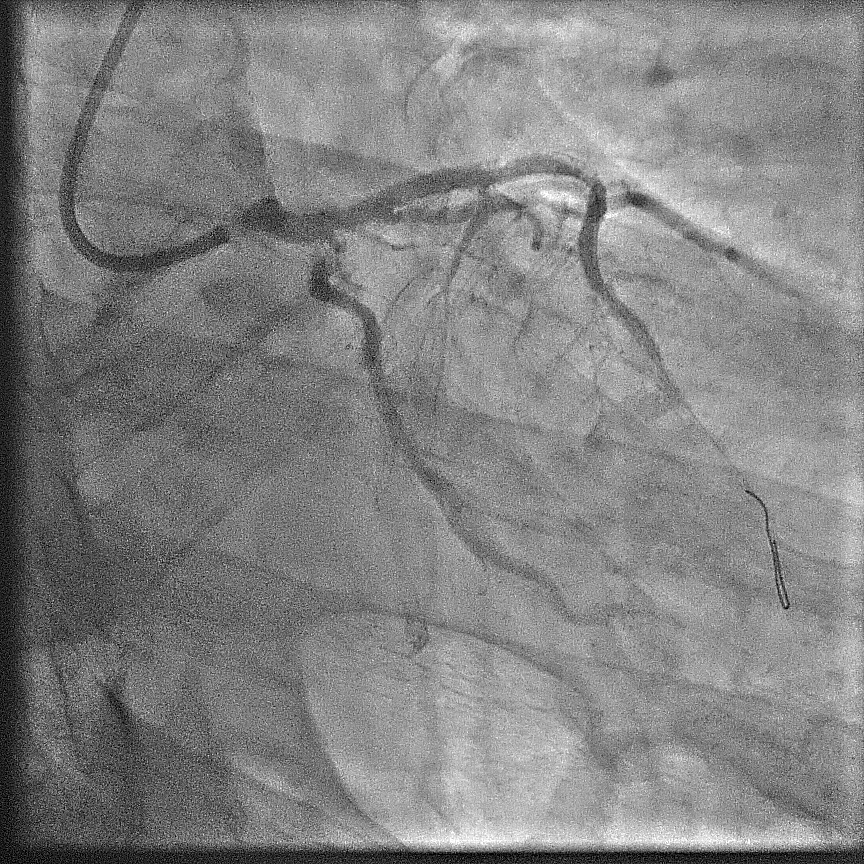

Angiography showed extensive calcification in the left and right coronary arteries, with severe stenosis at the left main ostium, severe in-stent restenosis at mid LAD, and severe, tortuous stenosis at the ostium and proximal LCx. The RCA was severely diffuse diseased with heavy calcification. The SYNTAX score was 58; BCIS CHIP score 7/13 - a very high risk and complex anatomy for PCI. STS surgery score risk for mortality was 3%; mortality and morbidity 18%.

The case was referred to cardiac surgeon. Due to extensive calcification of the aorta, surgery was deemed highly challenging. With surgery declined, a staged procedure of PCI and transcatheter aortic valve replacement (TAVR) was planned. Throughout, contrast use was minimized to reduce renal injury.First Procedure: Initial PCI targeted the left coronary system. Pre-dilation was performed at left main ostium, followed by at the most obstructive lesion in the LCx to reduce the risk of ischemia in subsequent interventions. The mid-LAD was treated with a drug-eluting balloon (DEB), followed by the LCx with DEB. Finally, the left main ostium was stented with a drug-eluting stent (DES), achieving a favourable outcome. Total contrast volume used was 28 mL.Second Procedure: The next day, PCI was performed on the RCA. Despite the challenging ostial lesion, positioning of the guiding catheter (AL1) was successful. Balloon pre-dilation and placement of two DESs in the proximal RCA achieved satisfactory result. Total contrast used was 31 mL. The patient experienced significant relief from angina following these interventions.One Month Later: TAVR was performed using an Evolut Pro+. Due to severe iliofemoral and aortic calcifications, device delivery was challenging. TAVR was ultimately succesful; peak aortic valve gradient was decreased from 50 mmHg to no residual gradient.